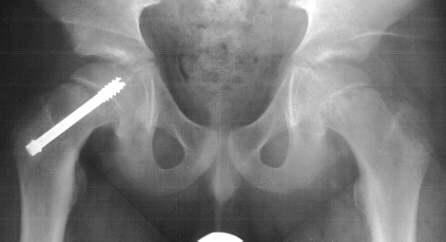

The patient was admitted to the hospital, placed on strict bedrest, and he had an in situ pinning of his right hip the next day. There were no postoperative complications, and he was discharged one day later. By the time of his follow-up visit three weeks later, he was riding his bike and had discarded his crutches. An AP pelvis and frog-leg lateral radiographs of both hips were obtained which were normal. At his three-month follow-up visit, the patient complained of a two week history of vague left hip pain. AP and frog-leg lateral radiographs revealed a grade 1 left slipped capital femoral epiphysis. He had an in situ pinning of his left hip the next day without complications .